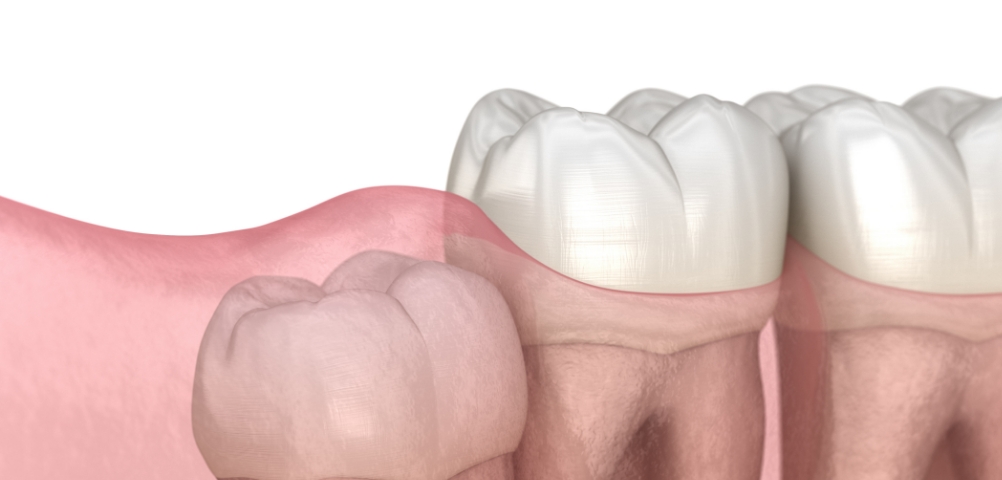

在进行根管治疗后, 为保护已变脆弱的牙齿,

通过整体包覆的方式进行修复,

是一种能同时恢复

受损牙齿功能的治疗,

并改善牙齿的美观效果